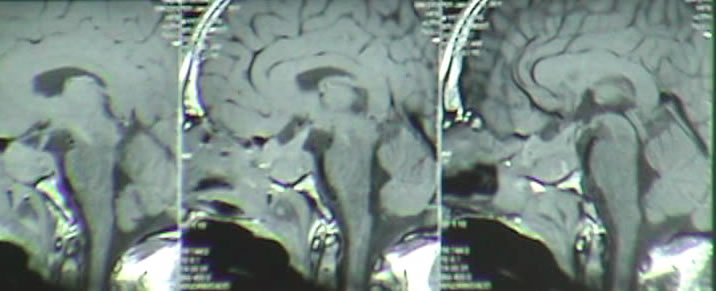

Fig-3: The next intraoperative MRI showing total resection of the mass and floating venous structures with deformed choroidal veins.

Fig-4: Saggital and coronal views showing the external drain  and  a clot over the mesencephalon.